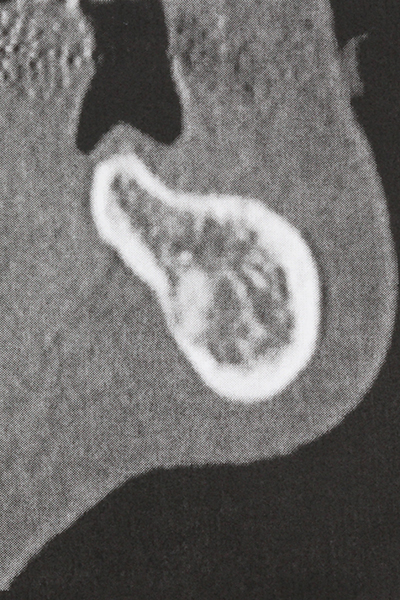

Indication: Sinus lift

Preparation of the lateral window during an external sinus floor elevation is challenging, particularly for implantologists with little surgical experience. Removal of the bone cover of the sinus without injuring the underlying Schneiderian membrane is only part of the operation – after establishing an adequate access, the membranous lining of the sinus must be carefully mobilized to make space for the augmentation materials or the implants. Piezosurgery is useful for this indication in two ways: diamond-coated instruments can be used for selective bone ablation and the underlying mucous membrane remains intact when the procedure is done carefully. The ultrasonic frequencies also enable detachment of the mucous membrane without complications – the frequencies are transmitted into the space between the mucous membrane and sinus floor by special blunt attachments (Cassetta, Ricci et al. 2012, Pereira, Gealh et al. 2014) (Rickert, Vissink et al. 2013). As a result, it is not surprising that current reviews of external sinus floor elevation positively evaluate the use of piezoelectric devices as well as the use of roughened implant surfaces and bone replacement materials (Wallace, Tarnow et al. 2012).